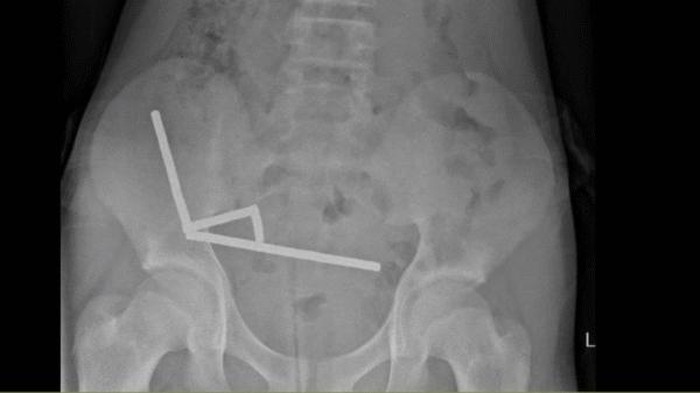

Ditulis Science Alert, magnet-magnet itu kemudian bersatu dan menghancur dalam tubuh bocah tersebut. Dengan menggunakan sinar X, dokter melihat empat rantai linier di bagian terpisah pada usus anak laki-laki itu.

Selama operasi, rantai-rantai tersebut ditemukan di beberapa bagian usus halus dan sekum. Rantai-rantai tersebut saling menekan dan menyebabkan beberapa bagian jaringan mati karena kekurangan darah, yang dikenal sebagai nekrosis tekanan.